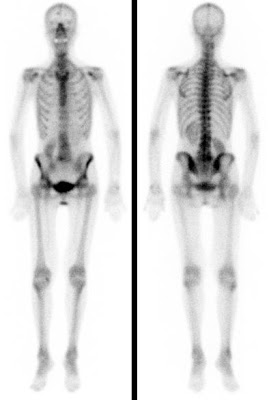

Bei der Skelettszintigraphie werden schwach radioaktiv markierte Phosphatkomplexe verabreicht, die zunächst im Blut durch den Körper zirkulieren und im Verlauf von 2-3 Stunden ausreichend in den Knochen eingebaut werden, so dass dann der Knochenstoffwechsel abgebildet werden kann.

Es bestehen die Möglichkeiten, gleich nach Verabreichung der Phosphatkomplexe die Durchblutung zu untersuchen und auf den Spätaufnahmen den Knochenumbau zu beurteilen. Bei der Skelettszintigraphie gibt es keine Unverträglichkeitsreaktionen auf die verabreichten Radiopharmaka. Im Gegensatz zu vielen Röntgenkontrastmitteln sind die verwendeten Radiopharmaka auch nicht nierenschädlich.

Die Hauptfragestellungen bei der Skelettszintigraphie betreffen die Feststellung evtl. Knochenmetastasen bei Krebserkrankungen und die Unterscheidung von primär entzündlichen vs. primär degenerativen Gelenkerkrankungen, also rheumatischen Grunderkrankungen mit Skelettbeteiligung vs. (aktivierten) Arthrosen.

Darüber hinaus ist die Skelettszintigraphie häufig auch bei der Abklärung unklarer Knochenschmerzen sehr hilfreich, etwa zur Feststellung evtl. Knochentumoren, von Prothesenlockerungen, einer Osteomyelitis, von Frakturen, von Knocheninfarkten etc.